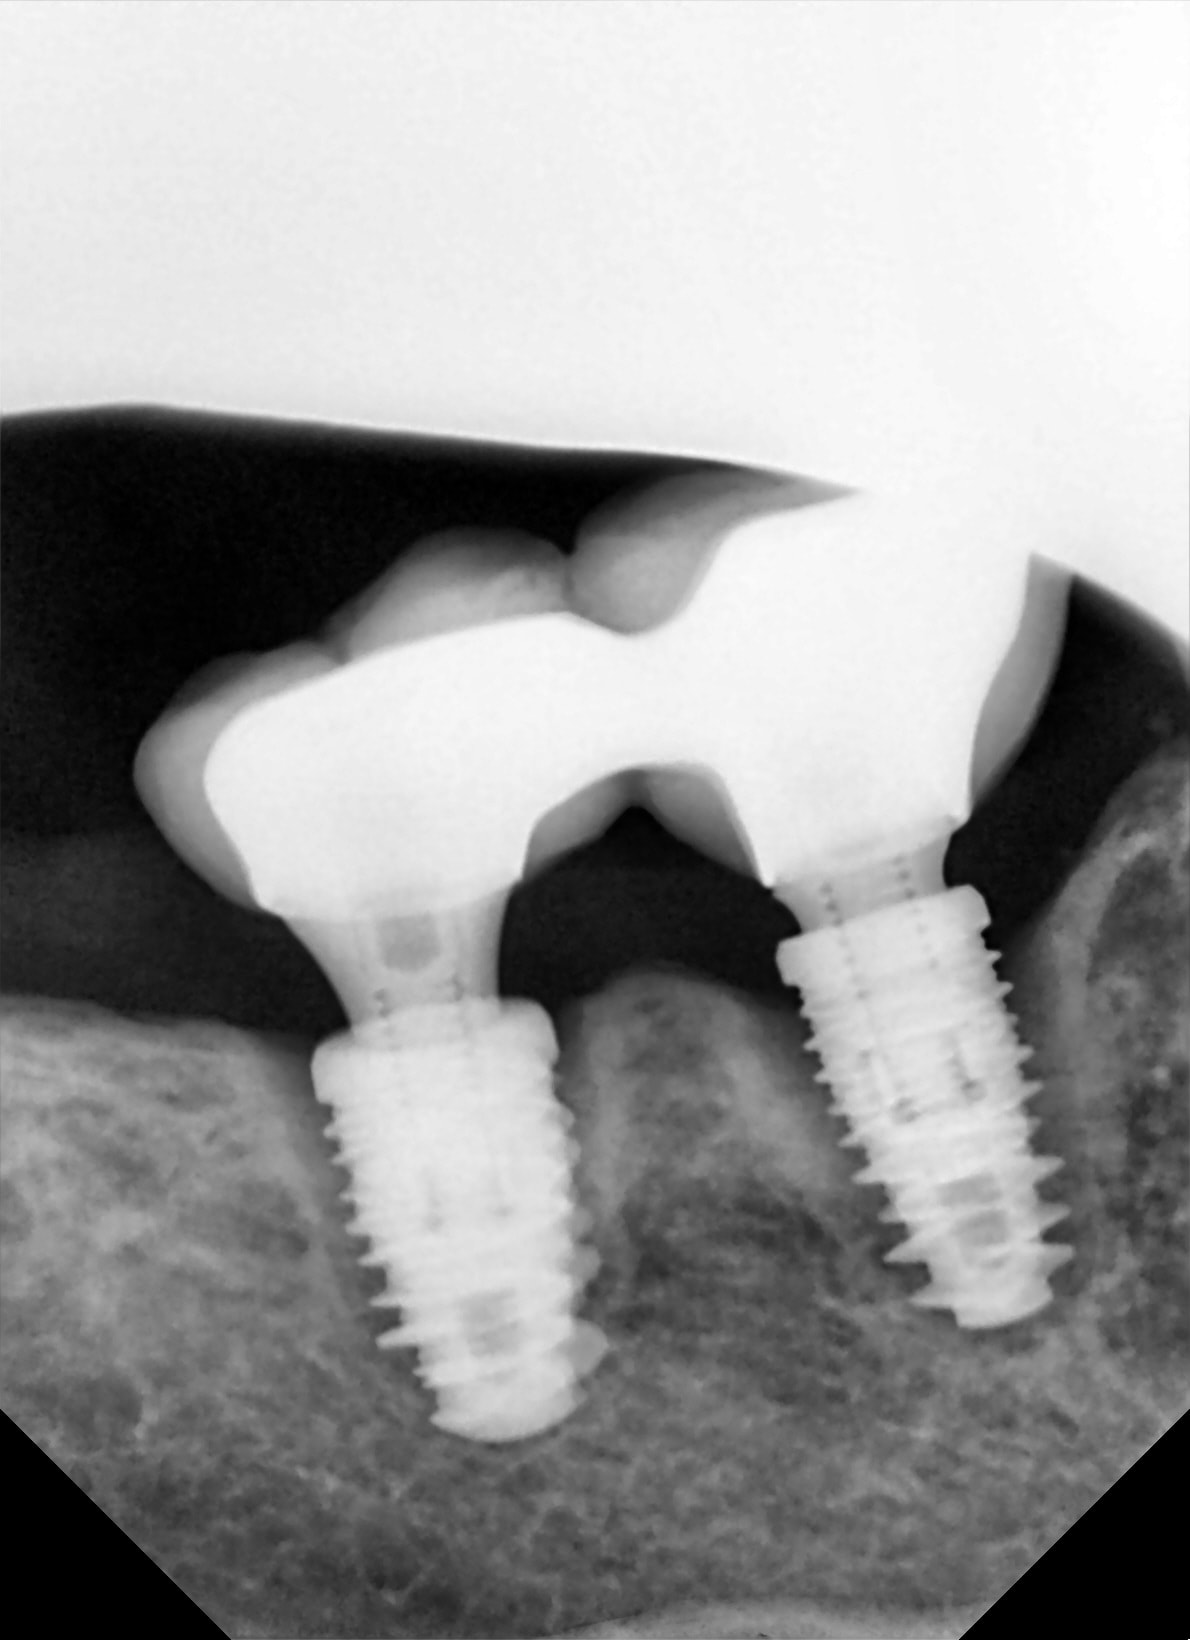

patiente avec pas mal d'implants. les autres nickel, jolie gencive.

Implant mis en charge il y a deux ans, juste avant la retraite du coupable.

" Elles ont toujours un peu bougé" qu'elle me dit

En largeur c'est une autoroute..

je replante direct après le curetage?

6 semaines après?